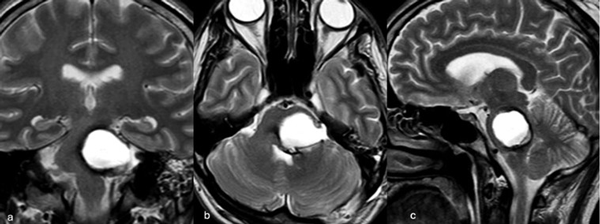

Caso 4: cavernoma bulbar

Una mujer de 53 años, con antecedentes de dos sangrados previos, consultó por un cuadro de perfil agudo caracterizado por tetraparesia asociada a compromiso de pares craneales bajos, que requirió instalación de una traqueostomía. La RM de encéfalo evidenció una malformación cavernomatosa en relación al bulbo izquierdo (Figura 9). Un mes después del último sangrado, la paciente fue sometida a una exéresis de la lesión mediante un abordaje suboccipital de línea media, vía intertonsilar (Figura 10), logrando una exéresis completa (Figura 11). Luego de la cirugía la paciente evolucionó con mejoría parcial de sus síntomas de ingreso, sin agregar nuevos déficits neurológicos.

Figura 9. RM preoperatoria de encéfalo. Se evidencia una lesión única intraaxial bulbotrigonal izquierda, que contacta la mitad inferior del piso del cuarto ventrículo, hiperintensa en T1 y T2, con vacíos de flujo que impresionan provenir de una malformación del desarrollo venoso, lo que sugiere una malformación cavernomatosa. A) Imagen en corte sagital ponderada en T1 posterior a la administración de gadolinio. B y C) Imágenes en corte axial ponderadas en T1 y T2, respectivamente.

Figura 10. Imágenes intraoperatorias bajo microscopía. Craneotomía suboccipital de línea media, con abordaje intertonsilar. A) Abordaje intertonsilar con disección telovelar hacia la derecha, abriendo el techo del cuarto ventrículo. B) Protrusión e identificación de la cápsula del cavernoma en relación al piso del cuarto ventrículo. C) Resección en bloque de la malformación cavernomatosa. D) Revisión del lecho, sin remanente.

Figura 11. RM postquirúrgica de encéfalo. Se evidencia una exéresis completa, sin daño del parénquima adyacente. A) Imagen en corte sagital ponderada en T1 posterior a la administración de gadolinio. B y C) Imágenes en corte axial ponderadas en T1 posterior a la administración de gadolinio y T2, respectivamente.